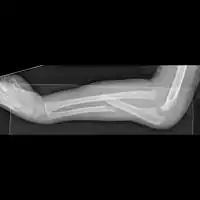

Monteggia fracture

Monteggia fractures may be managed conservatively in children with closed reduction (resetting and casting), but due to high risk of displacement causing malunion, open reduction internal fixation is typically performed.[4]

Osteosynthesis (open reduction and internal fixation) of the ulnar shaft is considered the standard of care in adults. It promotes stability of the radial head dislocation and allows very early mobilisation to prevent stiffness. The elbow joint is particularly susceptible to loss of motion.